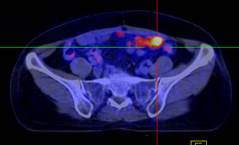

Hình 1. Bệnh nhân Nguyễn Th. H., nữ, 43 tuổi, chẩn đoán ung thư buồng trứng phải. Trên hình FDG-PET/CT thấy khối u buồng trứng phải tăng hấp thu FDG.

Hình 2. Bệnh nhân Lê Th. H., nữ, 58 tuổi, chẩn đoán: ung thư buồng trứng trái đã phẫu thuật và điều trị hóa chất năm 2011. Sau 8 tháng bệnh nhân kiểm tra thấy nồng độ chỉ điểm khối u CA 125 tăng cao (225ng/ml). Bệnh nhân được chỉ định chụp PET/CT kiểm tra. Trên hình PET/CT thấy tổn thương tái phát di căn màng bụng, trên hình CT không phát hiện được.